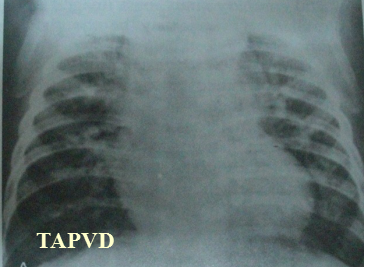

X-Ray --心脏形状